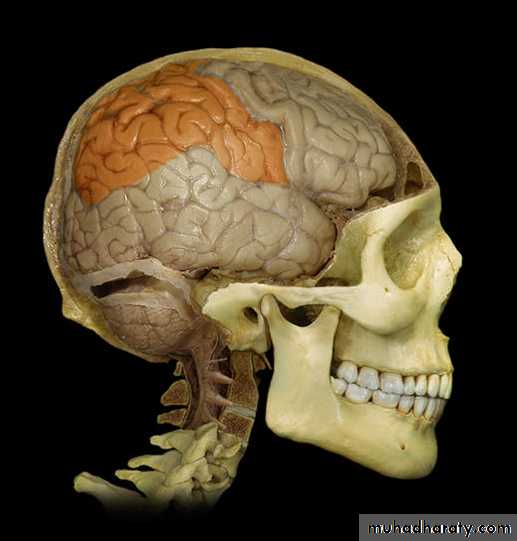

Lobes of Cerebral Hemisphere

Five lobes

Frontal lobe

Parietal lobe

Temporal lobe

Occipital lobe

Insular lobe

Parietal lobeOccipital lobe